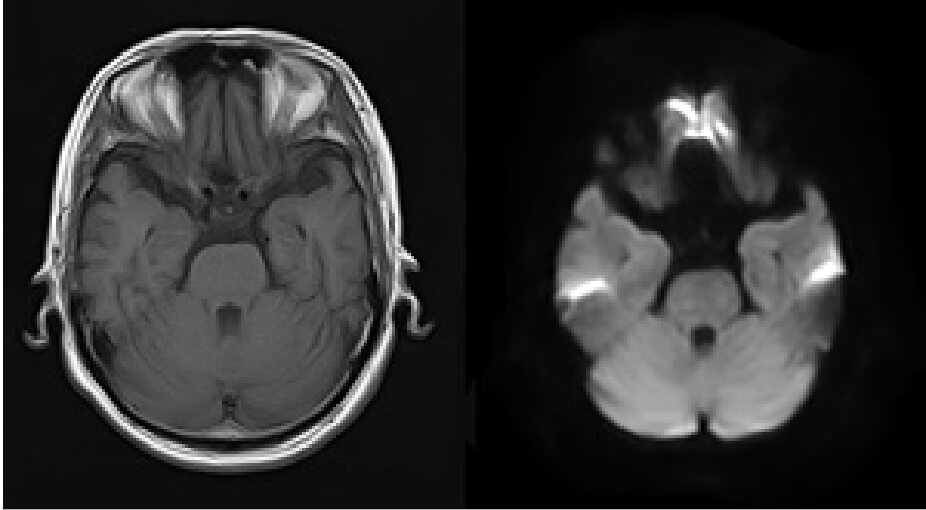

正常な脳のMRI画像2